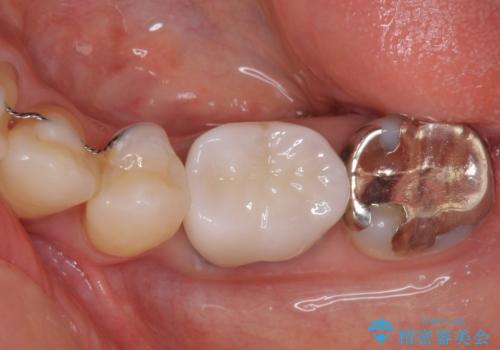

上唇小帯を切除したことで、ブリッジのダミー部分に触れて腫れていた歯肉は健全な状態になりました。

隙間もなくなったことで話す際の空気の漏れや、ものが挟まることもなくなりました。